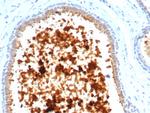

Mammaglobin (SCGB2A2) (Breast Cancer Marker) Antibody in Immunohistochemistry (Paraffin) (IHC (P))

图: 1 / 3

Mammaglobin (SCGB2A2) (Breast Cancer Marker) Antibody (4250-RBM11-P1ABX) in IHC (P)

Formalin-fixed, paraffin-embedded human lactating breast stained with Mammaglobin Recombinant Rabbit Monoclonal Antibody (MGB/4811R). {{ $ctrl.currentElement.advancedVerification.fullName }} 验证信息 View more